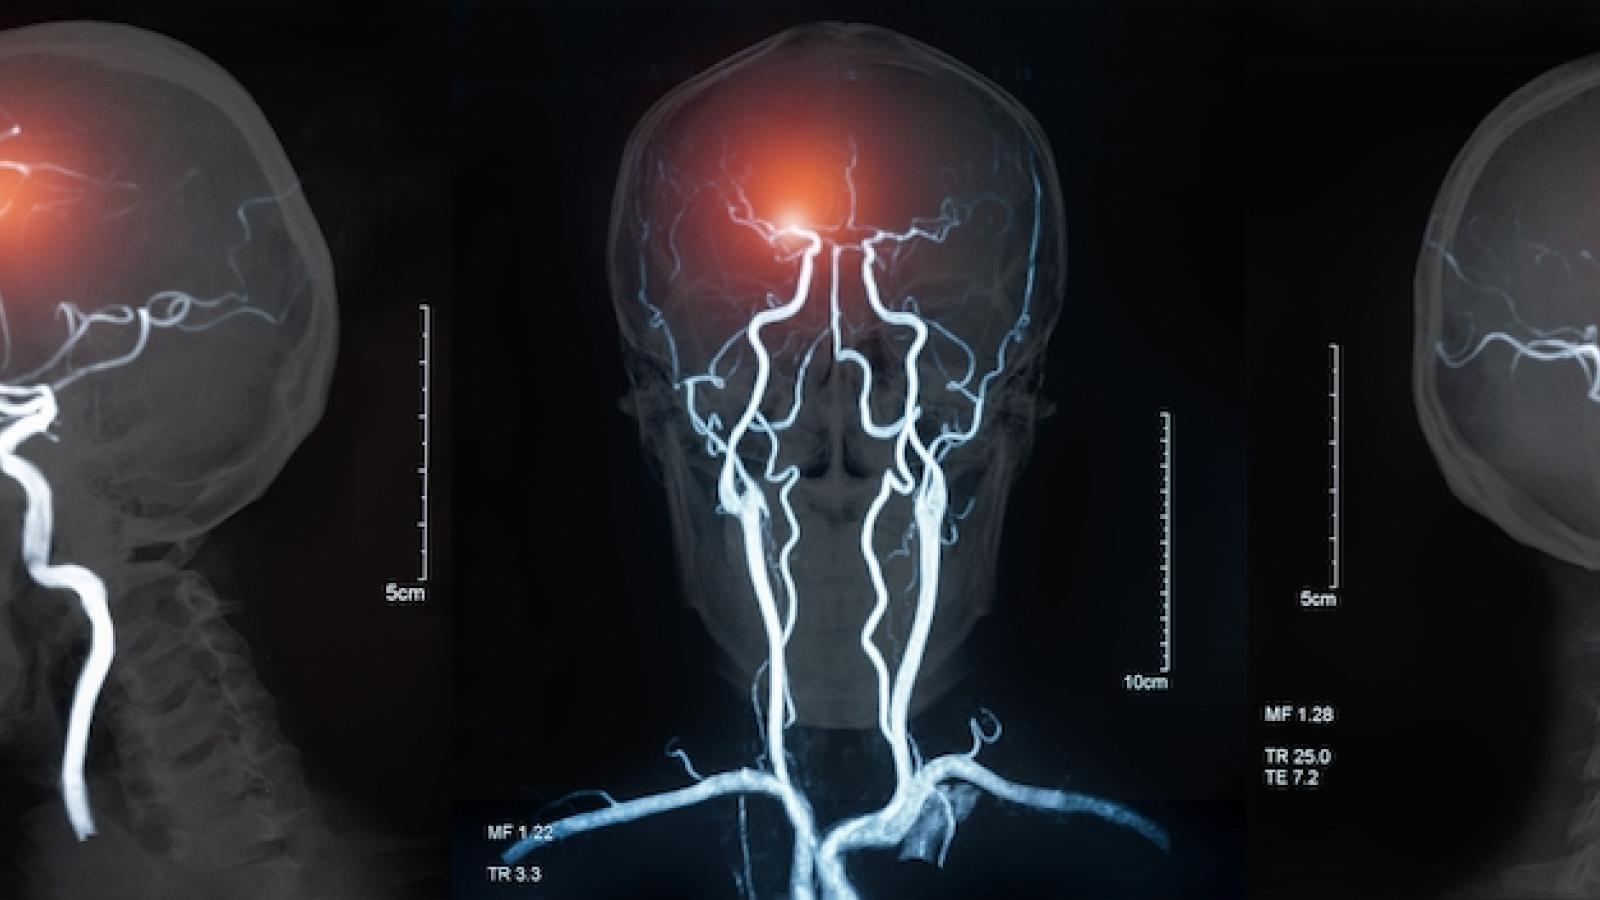

Two cheap and common drugs could be re-purposed as the first specific treatment for people who experience a type of stroke linked to nearly half of all dementias, according to the results of a trial led by Prof Joanna Wardlaw (UK DRI at Edinburgh), presented at the American Heart Association International Stroke Conference.

Lacunar strokes affect at least 25,000 people in the UK each year. They’re thought to be caused by cerebral small vessel disease (cSVD), where small blood vessels deep within the brain become damaged and stop working properly. Lacunar strokes can have distressing effects as people may develop problems with their thinking and memory, movement, and even dementia. There are currently no effective treatments.